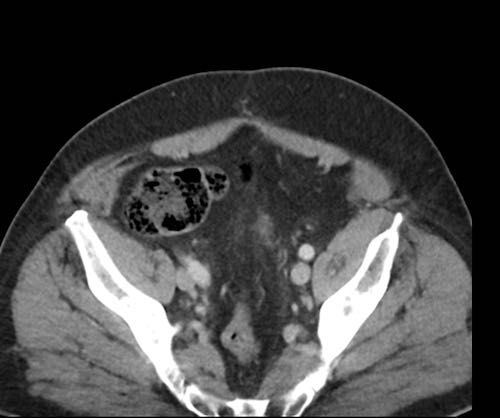

Ca lâm sàng 2

Cuộn qua các lát cắt.

Bạn có thể phát hiện tất cả các tổn thương cấy ghép phúc mạc không?

.jpeg)